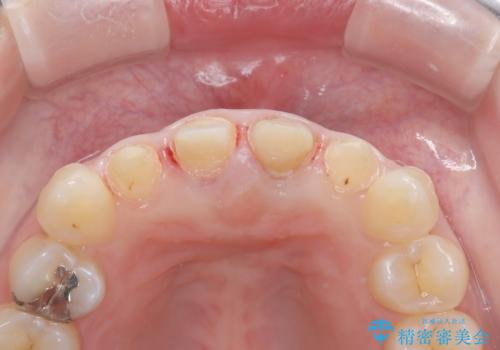

- 「前歯の色が気になる」を主訴に来院された患者様です。前歯が咬んでない開咬という状態のため、矯正治療を勧めましたが、患者様がご希望されなかったためオールセラミッククラウンで治療を行いました。右上1番は、神経の検査の結果、神経が死んでいたため根管療から行いました。左上1番は、金属の土台が入っていたのとラバーダムシートを使用せず根管治療が行われていたため、再度根管治療から行いました。その後ファイバーコアをたてオールセラミッククラウンで治療を行いました。

※根管治療では根管内に細菌を入れない事がとても大切なので必ずラバーダムシートとマイクロスコープを使用して根管治療を行っています。